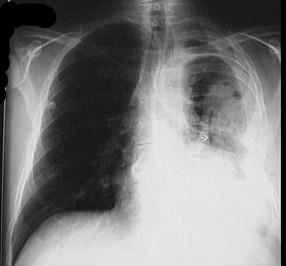

下列哪张图片是脓胸X线表现 ( )A、B、C、D、

问题 下列哪张图片是脓胸X线表现 ( )

选项 A、 B、 C、 D、

答案 B